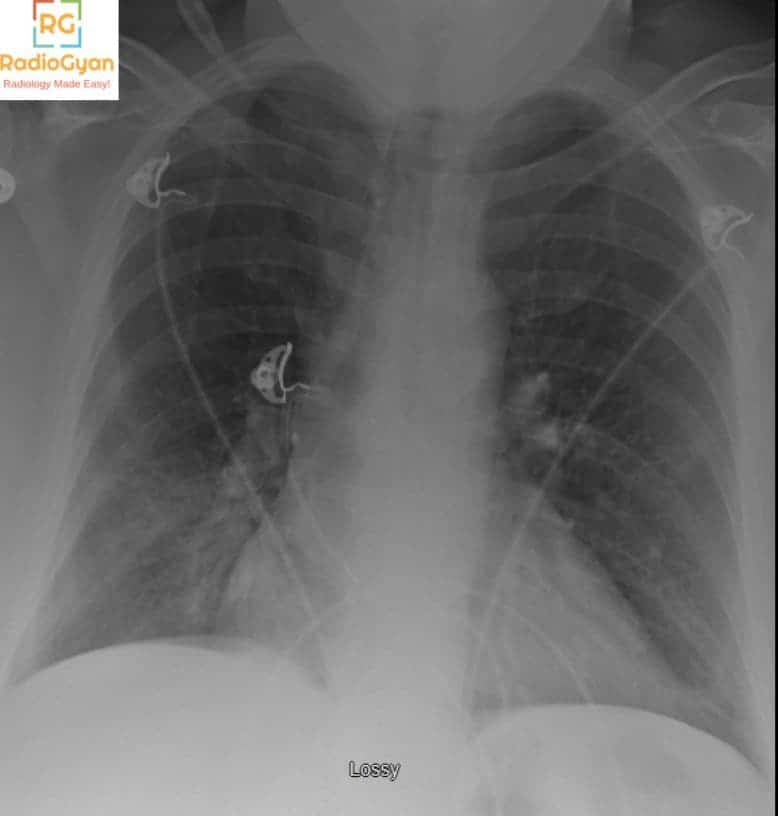

Have a look at the first image once again now. The RV: LV ratio is more than one and there is flattening of the interventricular septum suggestive of right ventricular strain indicating a poor prognosis. More than what meets the eye!ย

What is your diagnosis in this patient presenting with acute chest pain and breathlessness? You can answer in the comments or in theย radiology group

Pulmonary embolism diagnosis : Quiz case

Diagnosis?

PA chest radiograph of adult patient with over-penetration

it shows vertebral fixation for T10 to L2 by nails and plates

the cardio/thoracic ratio is slightly increased for correlation with echocardiography

right calcified hilar LN

Normal both lung fields

no pleural effusion

central mediation structures

both diaphragmatic copulae are smooth and normal in position

the bony thoracic cage show no gross abnormalities